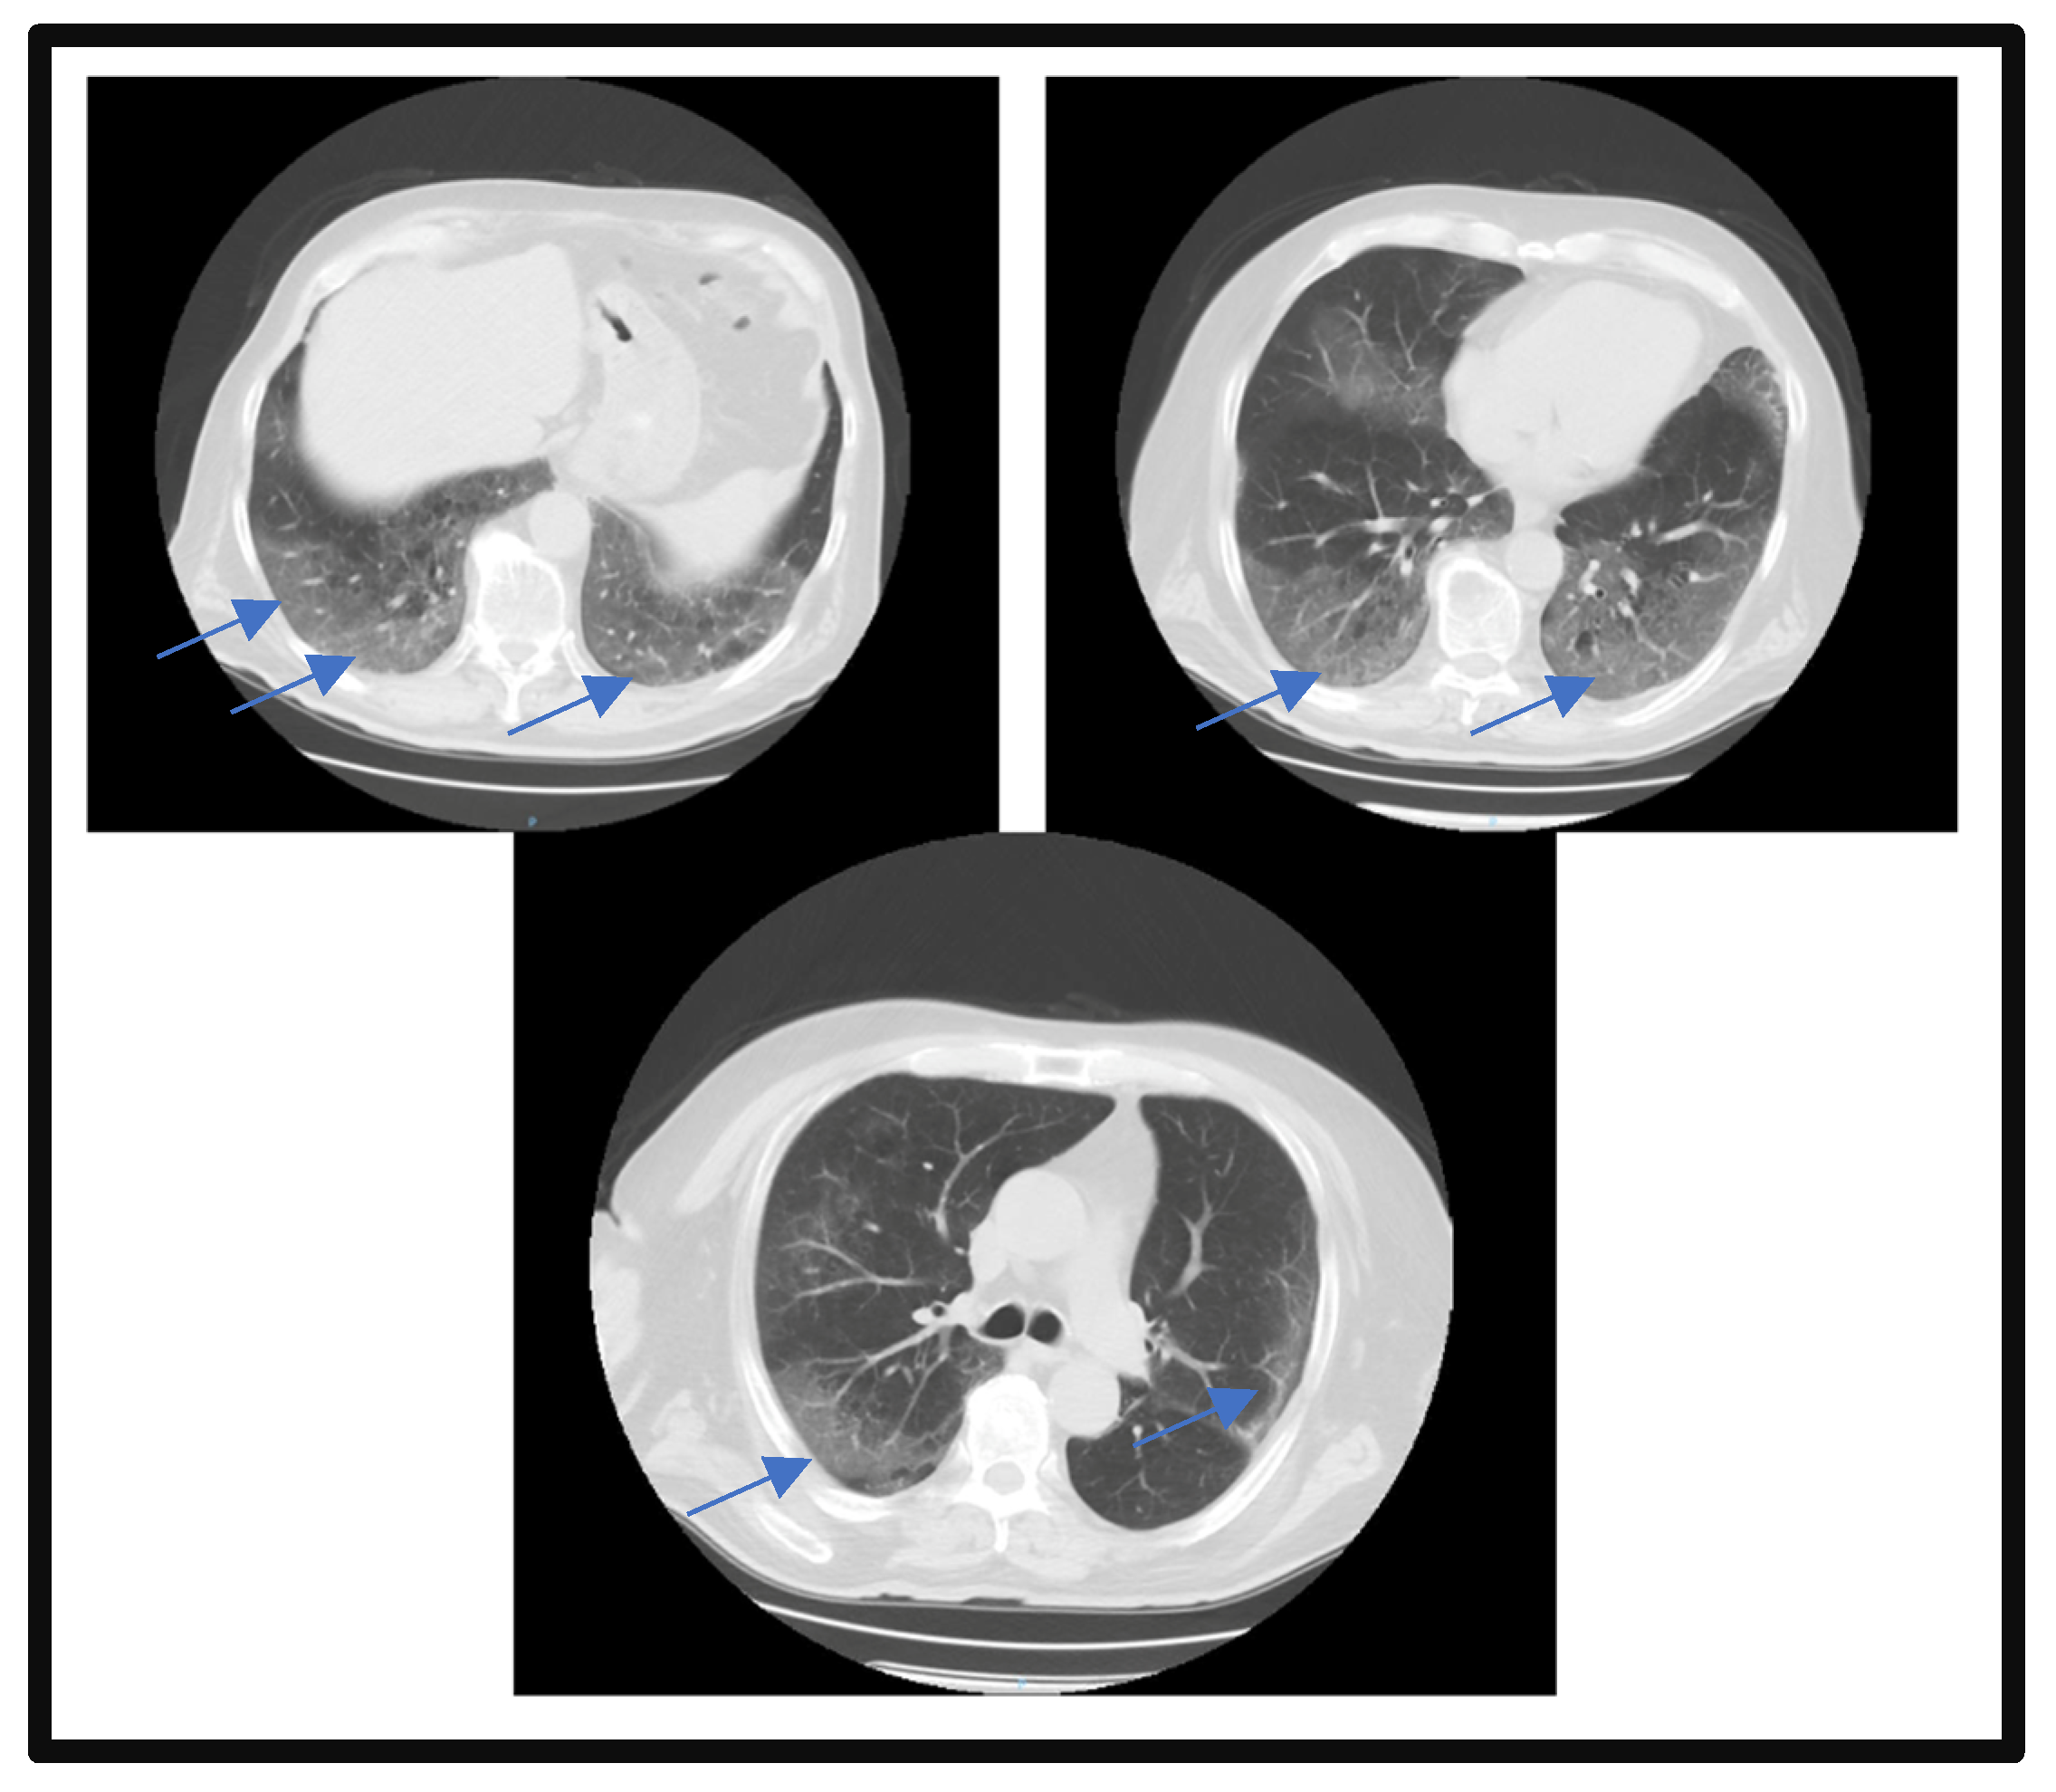

The patient presented with acute respiratory failure, which required oxygen therapy with a simple face mask with a flow rate of 5 L/minute and peripheral oxygen saturation of 96%. The patient required high-flow nasal oxygen therapy (with a flow rate of 60 L/minute) to manage the acute hypoxemic respiratory failure exacerbation during the first night of admission. On the third day of admission, a pulmonary CT scan re-evaluation was performed, which confirmed the aggravation of lung impairment (a severity score of 14 out of 25 was reported), which was also maintained at the last assessment on the fourteenth day of hospitalization (Figure 2).

Figure 2.

Pulmonary CT scan on the 3rd day of admission. Blue arrows highlight the lesion areas of condensation in the matt glass aspect.